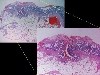

A case of IIc type early gastric cancer with dermatomyositis.

Histology

Histopathological Classifications

Malignant epithelial tumor/Adenocarcinoma